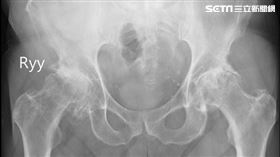

愛喝酒+運動過度 男子大腿骨全壞死

61歲德國籍的K先生,在台工作定居數十年,32歲就開...